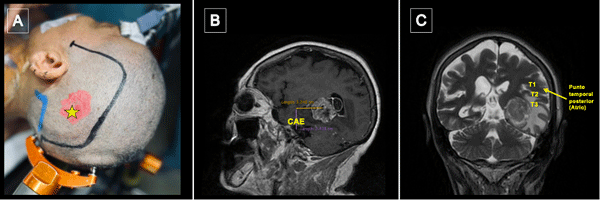

La resonancia magnética (RM) de encéfalo con gadolinio evidenció una lesión expansiva heterogénea, con áreas centrales de aspecto quístico y degeneración necrótica, localizada en la topografía temporomesial izquierda de aproximadamente 28 × 27 mm en plano axial y 29 × 26 mm en plano coronal, con realce heterogéneo tras la administración de contraste endovenoso. En secuencia de susceptibilidad magnética presentaba signos de restos de hemosiderina y/o microcalcificaciones. En el asta occipital y el atrio ipsilateral del ventrículo lateral, se evidenciaron formaciones quísticas con refuerzo periférico. La lesión descripta presentaba edema perilesional que comprometía el lóbulo temporal izquierdo y la región parietoccipital ipsilateral. Además, se observó dilatación del tercer ventrículo y ventrículo lateral homolateral. Las cisternas perimesencefálicas se encontraban libres, y las estructuras de la línea media, centradas. Las imágenes obtenidas eran sugestivas de una lesión de origen glial de alto grado (Figura 1). Se complementó con tractografía en la que se observó una disminución de la fracción de anisotropía a nivel del septum sagital con disrupción de las fibras de los tractos arcuato, frontooccipital inferior y longitudinal inferior izquierdo (Figura 2).

Figura 2. Tractografía con reconstrucción 3D de los fascículos asociados. Disminución de la fracción de anisotropía a nivel del septum sagital con disrupción de las fibras de los tractos A) Arcuato izquierdo. B) Frontooccipital inferior izquierdo. C) Longitudinal inferior izquierdo.